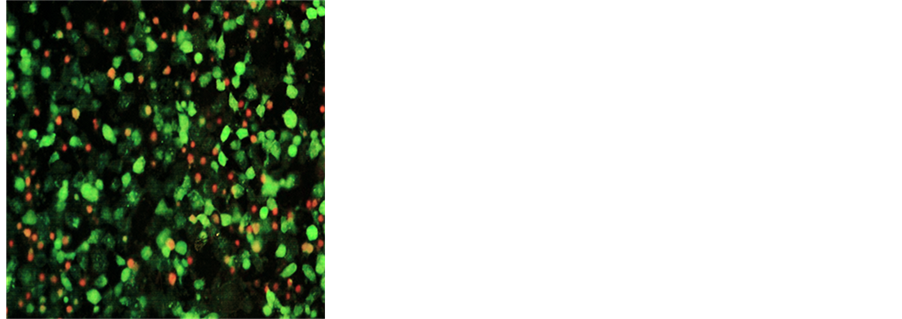

2.4. Live Green Caspase Assay

The cells were grown to confluence and either left in media alone or challenged with the NM dissolved in media at 100, 500 and 1000 μg/ml and incubated for 24 hours. The cell culture was washed with PBS and treated with the caspase reagent as specified in the manufacturer’s protocol (Molecular Probes Image-IT Live Green Poly Caspases Detection Kit 135104, Invitrogen). The cells were photographed under the fluorescence microscope and counted. Green colored cells represent viable cells, while orange and red colors represent early and late apoptotic cells respectively.

3.2. Nutrient Mixture Induced Apoptosis through Induction of Caspases

Quantitative analysis of DU-145 cells in early and late apoptotic stages was done by using the Live Green Caspase assay. Analysis with Live Green Caspase detection kit revealed a dose dependent increase in apoptosis of DU-145 cells with slight apoptosis found at 100 μg/ml, moderate at 500 μg/ml and significant at 1000 μg/ml

NM. Quantitative analysis of the data revealed the percentage of apoptotic cells to be 6% at 100 μg/ml (all in early phase apoptosis), 49% at 500 μg/ml (10% in early phase; 39% in late phase) and 83% for 1000 μg/ml NM (8% in early phase; 75% in late phase). It was observed that there was a corresponding decrease in percentage of live cells and an increase in percentage of cells in late apoptotic stages with increasing NM concentrations. A quantitative analysis of apoptosis induction in normal human dermal fibroblasts showed equivalency to DU-145 cells at 100 μg/ml. However, at higher concentrations of NM the induction of apoptosis was significantly lower in NHDF cells as compared to DU-145 cells. The percentage of apoptotic NHDF cells was 7% at 100 μg/ml (2% in early phase, 5% in late phase), 25.6% at 500 μg/ml (4.6% in early phase, 21% in late phase) and 76.5% at 1000 μg/ml (23.5% in early phase, 53% in late phase). Photomicrographs of apoptotic DU-145 cells and NHDF are shown in Figures 2(a)-(d) and Figures 3(a)-(d), respectively. The quantitative analysis of live, early and late DU-145 prostate cancer cells and NHDF cells are shown in Figure 2(e) and Figure 3(e), respectively.

Figure 2. Effect of NM on induction of apoptosis in prostate cancer DU-145 cells. Photomicrographs of DU-145 cells (×20 magnification) treated with (a) 0 mg/ml, (b) 100 mg/ml, (c) 500 mg/ml, (d) 1000 mg/ml concentrations of NM respectively. (e) Analytical representation of the differential distribution of cells in early or late phases of apoptosis upon treatment with 0, 100, 500 and 1000 mg/ml NM concentrations.